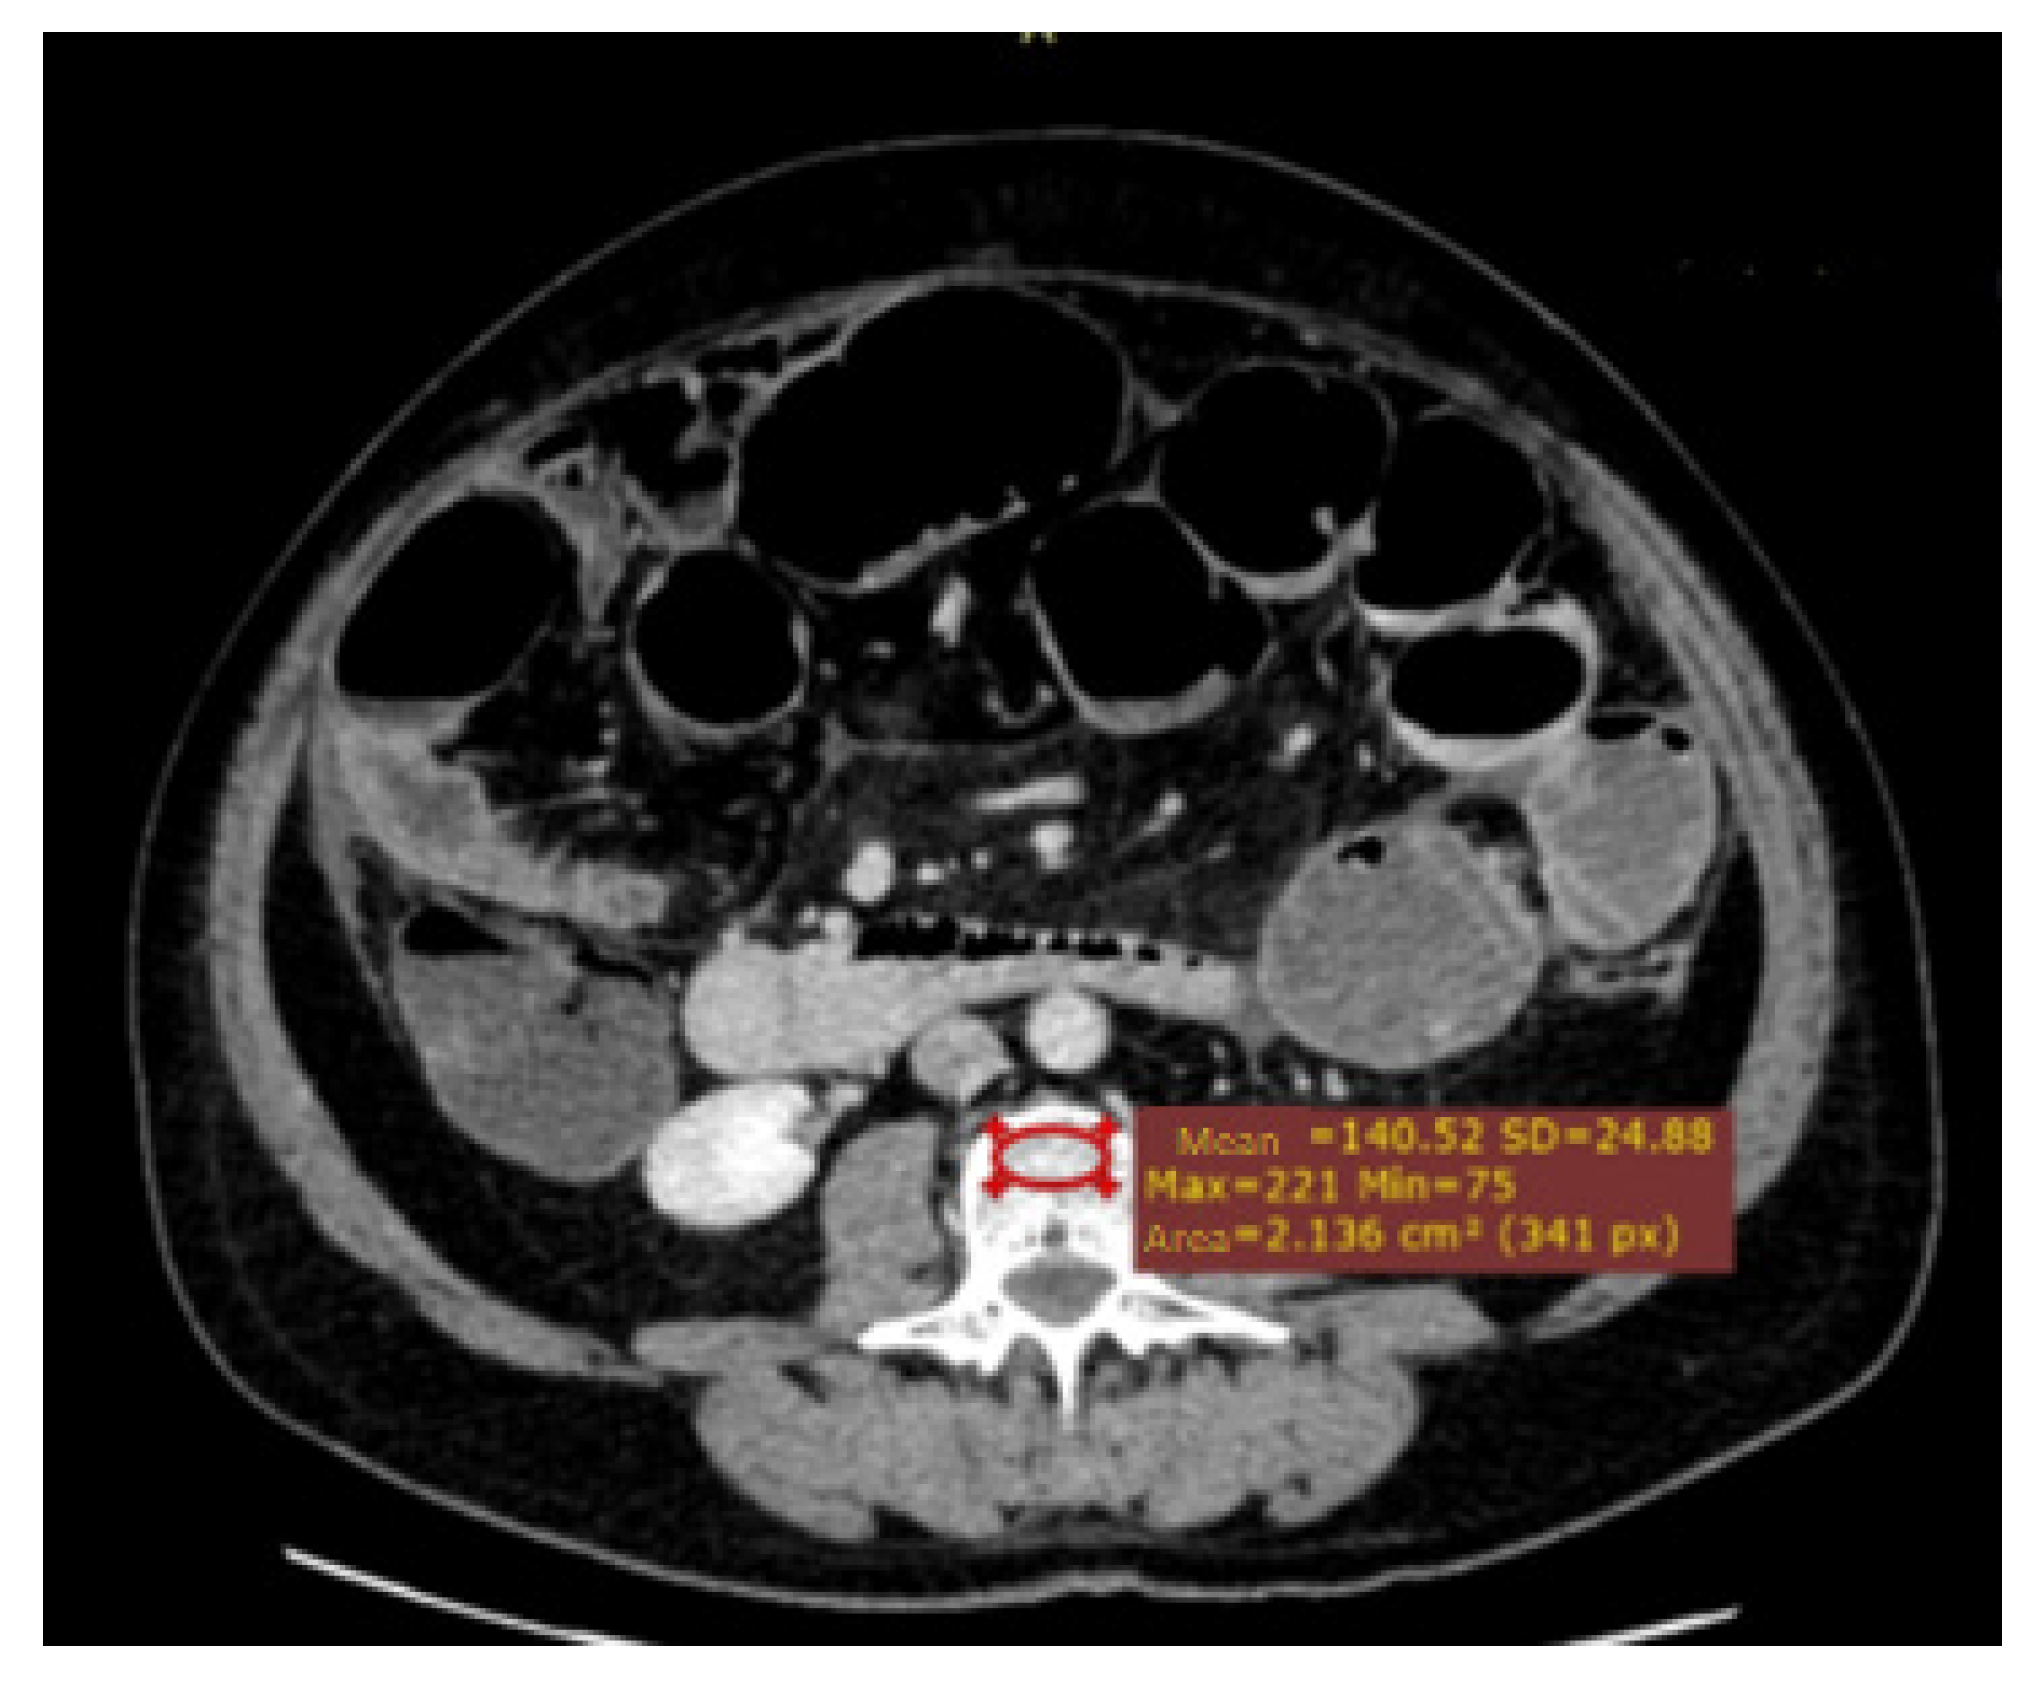

| Median osteopenia in ROI at L3 (IQR) (HU) | 138.1 (102.1–181.0) | 144.0 (109.6–193.8) | 100.6 (74.6–142.5) | <0.001 |

| Number of patients with osteopenia under cut-off point | 61 (23.4%) | 38 (17.7%) | 23 (50.0%) | <0.001 |